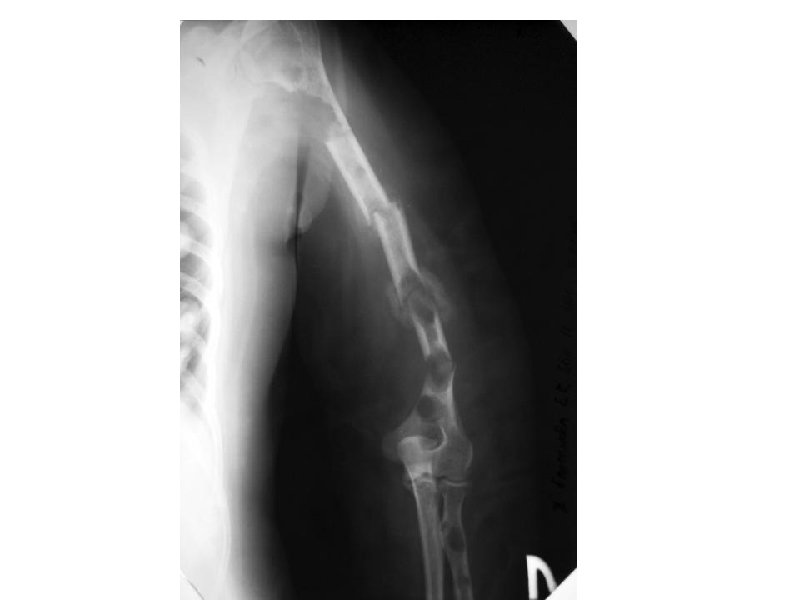

Клинические проявления ММ • Множественные остеолитические очаги Поражение костей повреждения плоских костей и эпифизов трубчатых костей • Диффузный остеопороз (остеопения) • Костные переломы • Уменьшение роста (вертебральный коллапс) Эффекты, ассоциированные с остеодеструкцией Внекостные плазмацитомы • Болевой синдром у 20 -40% Гиперкальциемия ( утомляемость, жажда, тошнота, запоры, повреждение почек, полиурия, сонливость, судороги, кома) • Гиперкальцийурия • Вовлечение мягких тканей преимущественно в области головы/шеи, очаги в печени, почках,

А- рентгенограмма, В- мультидетекторная КТ (МДКТ), Смагнитнорезонансная томография (МРТ)

А-ренгенограмма, В-МДКТ